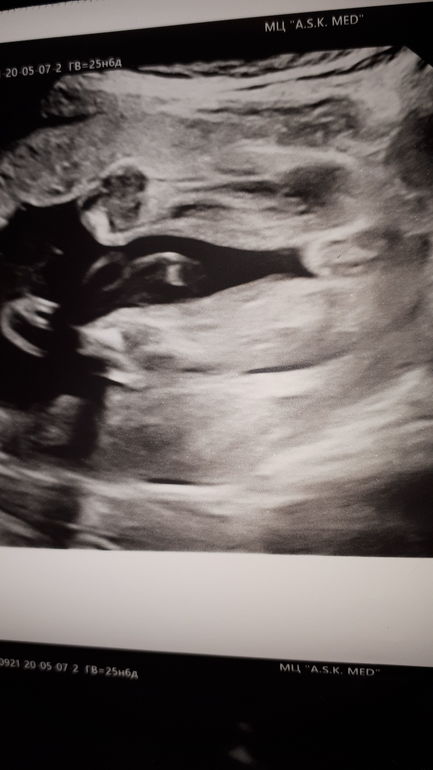

Ирина 6 лет Узи 24 недели и 2 дня Точно девчуля? Посмотрите еще 20 записей на эту тему Отменить Ответить Ирина Тайна раскрыта 11.08.20,у меня доченька родилась,очень люблю ее,пусть растет здоровенькой💋💋💋💋💋 13.08.2020 Ответить Nikino Похоже на девочку.) У мальчиков, обычно писюн торчит даже с нижнего ракурса. 07.05.2020 Ответить Ирина Спасибо большое))) 07.05.2020 Ответить Мили Ну прям пирожок 😊 07.05.2020 Ответить Ирина Ошибки быть не может?) 07.05.2020 Ответить Мили Я, конечно, не узист, но вижу девочкины поичиндалы) 07.05.2020 Ответить Ирина Спасибо большое))) 07.05.2020 Ответить Я знаю почему у сердца четыре камеры Очень похоже)) 07.05.2020 Ответить На память) Длина цикла Чаты Беременных Выберите чат: Январята-2026 Февралята-2026 Мартята-2026 Апрелята-2026 Майчата-2026 Июнята-2026 Июлята-2026 Августята-2026